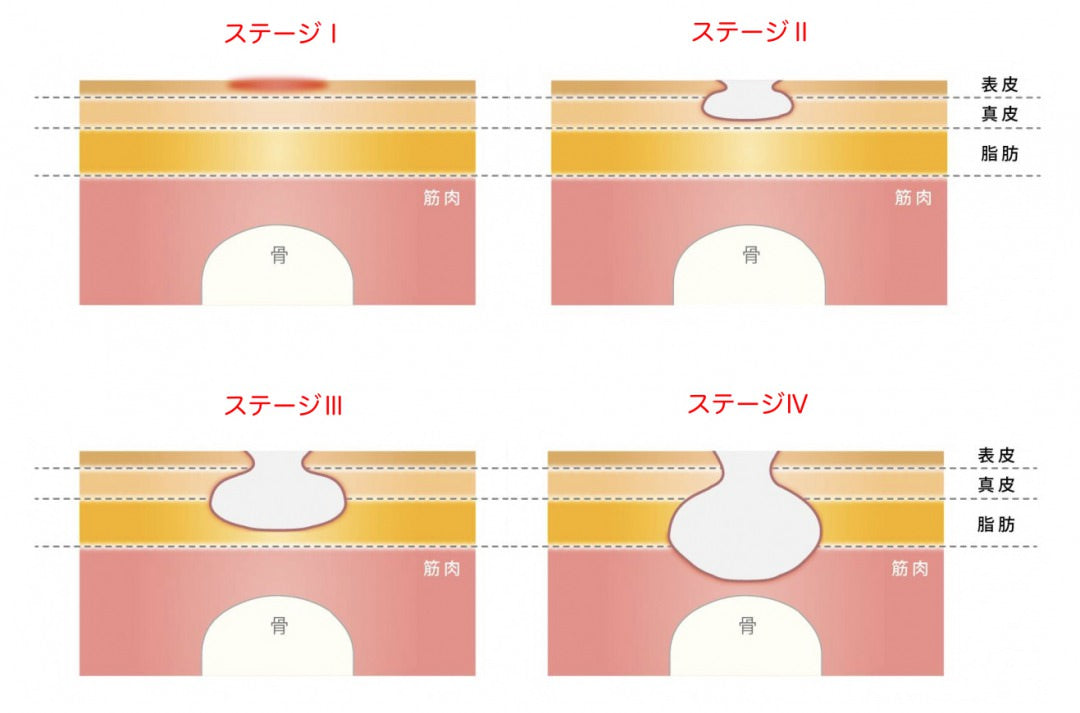

褥瘡の重症度分類を理解しようステージ分類NPUAP、EPUAP分類。

急性期の褥瘡と慢性期の褥瘡とは浅い褥瘡、深い褥瘡進展過程。

急性期の褥瘡と慢性期の褥瘡とは浅い褥瘡、深い褥瘡進展過程。